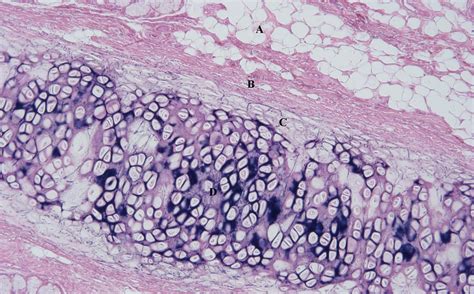

To appreciate the significance of the elastic cartilage location, one must first understand what makes this tissue fundamentally different from its counterparts. Elastic cartilage is characterized by the presence of a yellow, thread-like network of elastin fibers. These fibers permeate the extracellular matrix, which is also populated by chondrocytes—the cells responsible for maintaining the cartilage.

The primary distinguishing features include:

• High Flexibility: It can withstand significant mechanical deformation without losing its structural integrity.

• Chondrocyte Density: The cells are more closely packed together compared to hyaline cartilage.

• Yellow Appearance: Due to the high concentration of elastin fibers, the tissue appears yellowish in a fresh state compared to the pearly white of hyaline cartilage.

• elastic cartilage under microscope